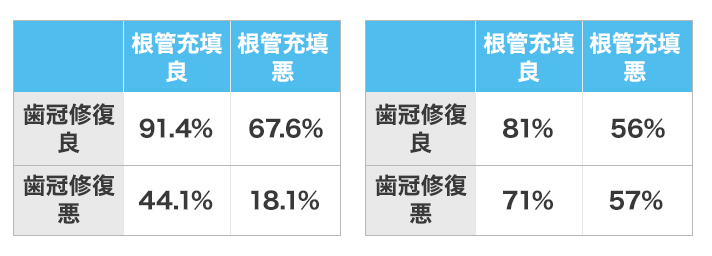

精密根管治療は通常の治療とは違い、根っこの治療・被せもの治療・歯周外科治療、この3つの精度で成功率と再発率が格段に変わります。イースト歯科ではこの3つ全ての治療においては精密かつ、丁寧な施術を得意としております。まずはドクターのご相談ください。

これは過去アメリカでの精密根管成功率の研究結果のデータになります

| 根管治療の精度 | 被せ物の精度 | 根管治療成功率 | |

| Case1 | 〇 |

〇 |

91.4% |

| Case2 | × |

〇 |

67.6% |

| Case3 | 〇 |

× |

44.1% |

| Case4 | × |

× |

18.1% |

「根管治療」、「被せ物治療(補綴)」、「歯周形成外科」この3つが機能すると成功します。

・まず根管治療で大事なのは、根管の土台を整えることです。

・次に内部を綺麗に洗浄して細菌を除去する

そして今後細菌に感染しないようにお薬を塗ります。

この状態が整った状態で根管充填をする という流れになります(完全密閉の状態)これが出来るか出来ないかでで根管治療の成功率は大きく変わます。

予後にならない為には、

1.術前根尖病変の存在がないこと

2.根尖から2mm以内根管充填

3. 空隙のない根管充填

4.適合の良い歯冠修復

ここが最も重要になります。

根っこの治療で発症する病気は虫歯です。虫歯になる理由は、接着剤が溶けて隙間からバイキンが入り病気になるケースがほとんどです。ですので治療時に隙間を作ってしまうとこういった病気のリスクを伴います。

引用元 Ray HA Trope M Int Fndod J1995

根管治療を成功に導くためには

1.歯の上を削る際、健全な歯が2mm必要であり厚みが1mmあることも前提となります。

2.歯の根っこを広げてバイ菌を取り出し、歯の中のバイ菌量を減らすこと。

3.この状態で封鎖する、ここで隙間なく完全密閉させることで治療の成功率が大きく変わります。その際フェルールを使用します。

この『根っこ』の治療と『被せ物』が完璧に行うのが本当の細密根管治療となります。片方の治療が優れていたとしても、治療後、予後になる可能性が高まり再度治療のリスクを伴います。当医院は治療の成功率を最大限高めるために『根っこ』と『被せ物』の治療をどちらも重要視して行っています。